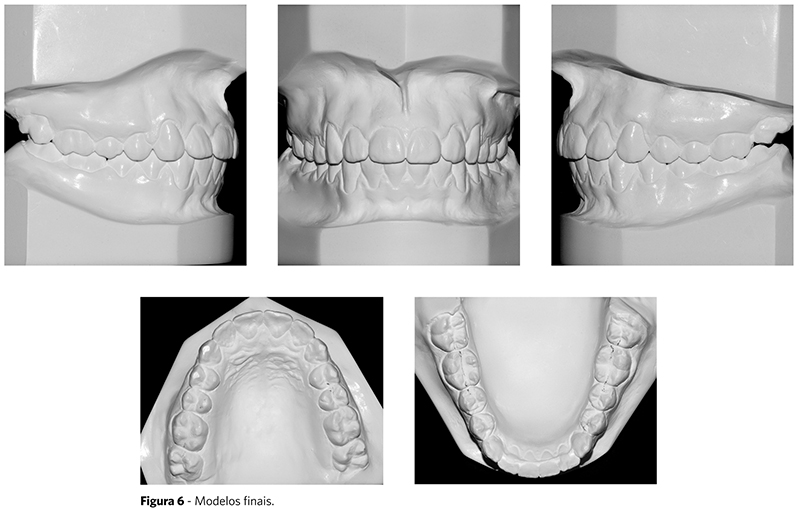

Após dois anos e dois meses de tratamento, os objetivos propostos foram alcançados, observando-se bom relacionamento dentário. Os lábios foram posicionados mais anteriormente devido à projeção dos incisivos, o que pode ser observado nas fotografias faciais ao final do tratamento (Fig. 5) e na sobreposição total dos traçados cefalométricos (Fig. 9).

As fotografias intrabucais mostram a correção da sobremordida e da inclinação dos incisivos (Fig. 5). Na arcada inferior, obteve-se o nivelamento da curva de Spee, além da manutenção das distâncias intercaninos e intermolares. Apesar da inclinação um pouco acentuada dos incisivos inferiores, a avaliação clínica mostrou periodonto saudável, pois a paciente apresentava, ao início, boa espessura de gengiva inserida.